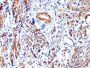

IHC, FFPE (verified), WB (verified)

Positive Control

Uterus, Blood vessels in all tissues, smooth muscle or leiomyosarcoma

IHC (FFPE) (verified)|WB (verified)